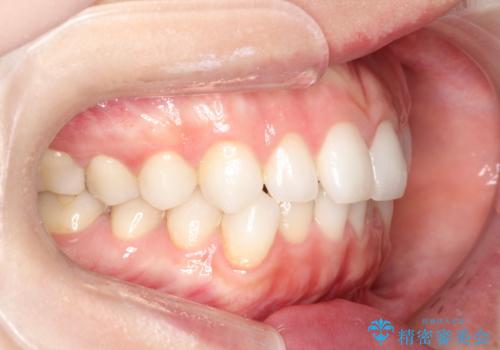

前歯のがたつきをインビザラインで目立たず矯正治療

- 上下の前歯のがたつきを主訴に来院されました。

目立たない装置がご希望で、インザラインによるマウスピース矯正にて治療を行うこととなりました。